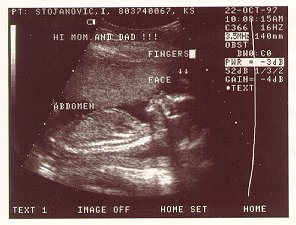

Ovo je prva slika gde se ja zaista vidim. To je ultrazvuk od 18-te nedeqe.

This is the first picture that you can actualy see me. It is 18th week ultrasound.